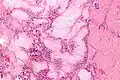

Micrograph of a gouty tophus -